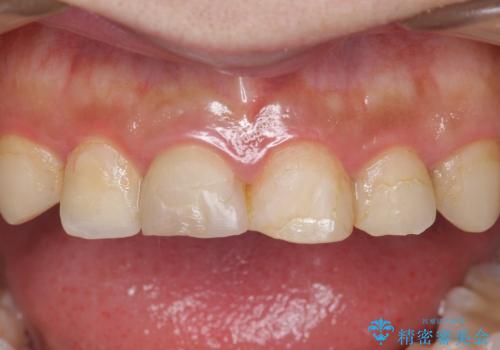

- 憧れの芸能人(ヴィジュアル系バンドマン)のような歯になりたいとのご希望で来院された患者様です。

咬み合わせが悪く矯正も検討されていたそうですが、歯を真っ白にしたいというご希望もあり、28本のすべての歯をセラミックにしたいとのことでした。

精査したところ、ほとんどの歯が保険内のレジンで充填されており、咬み合わせも悪く咬合していない歯もありました。